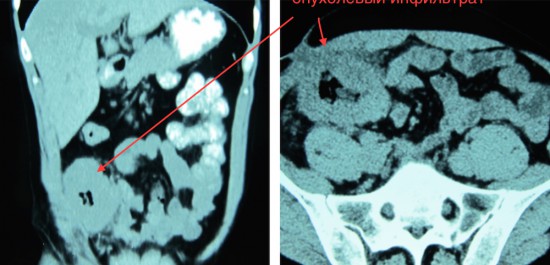

Рецидив рака слепой кишки

Отделение опухоли от наружных подвздошных сосудов и нижней полой вены